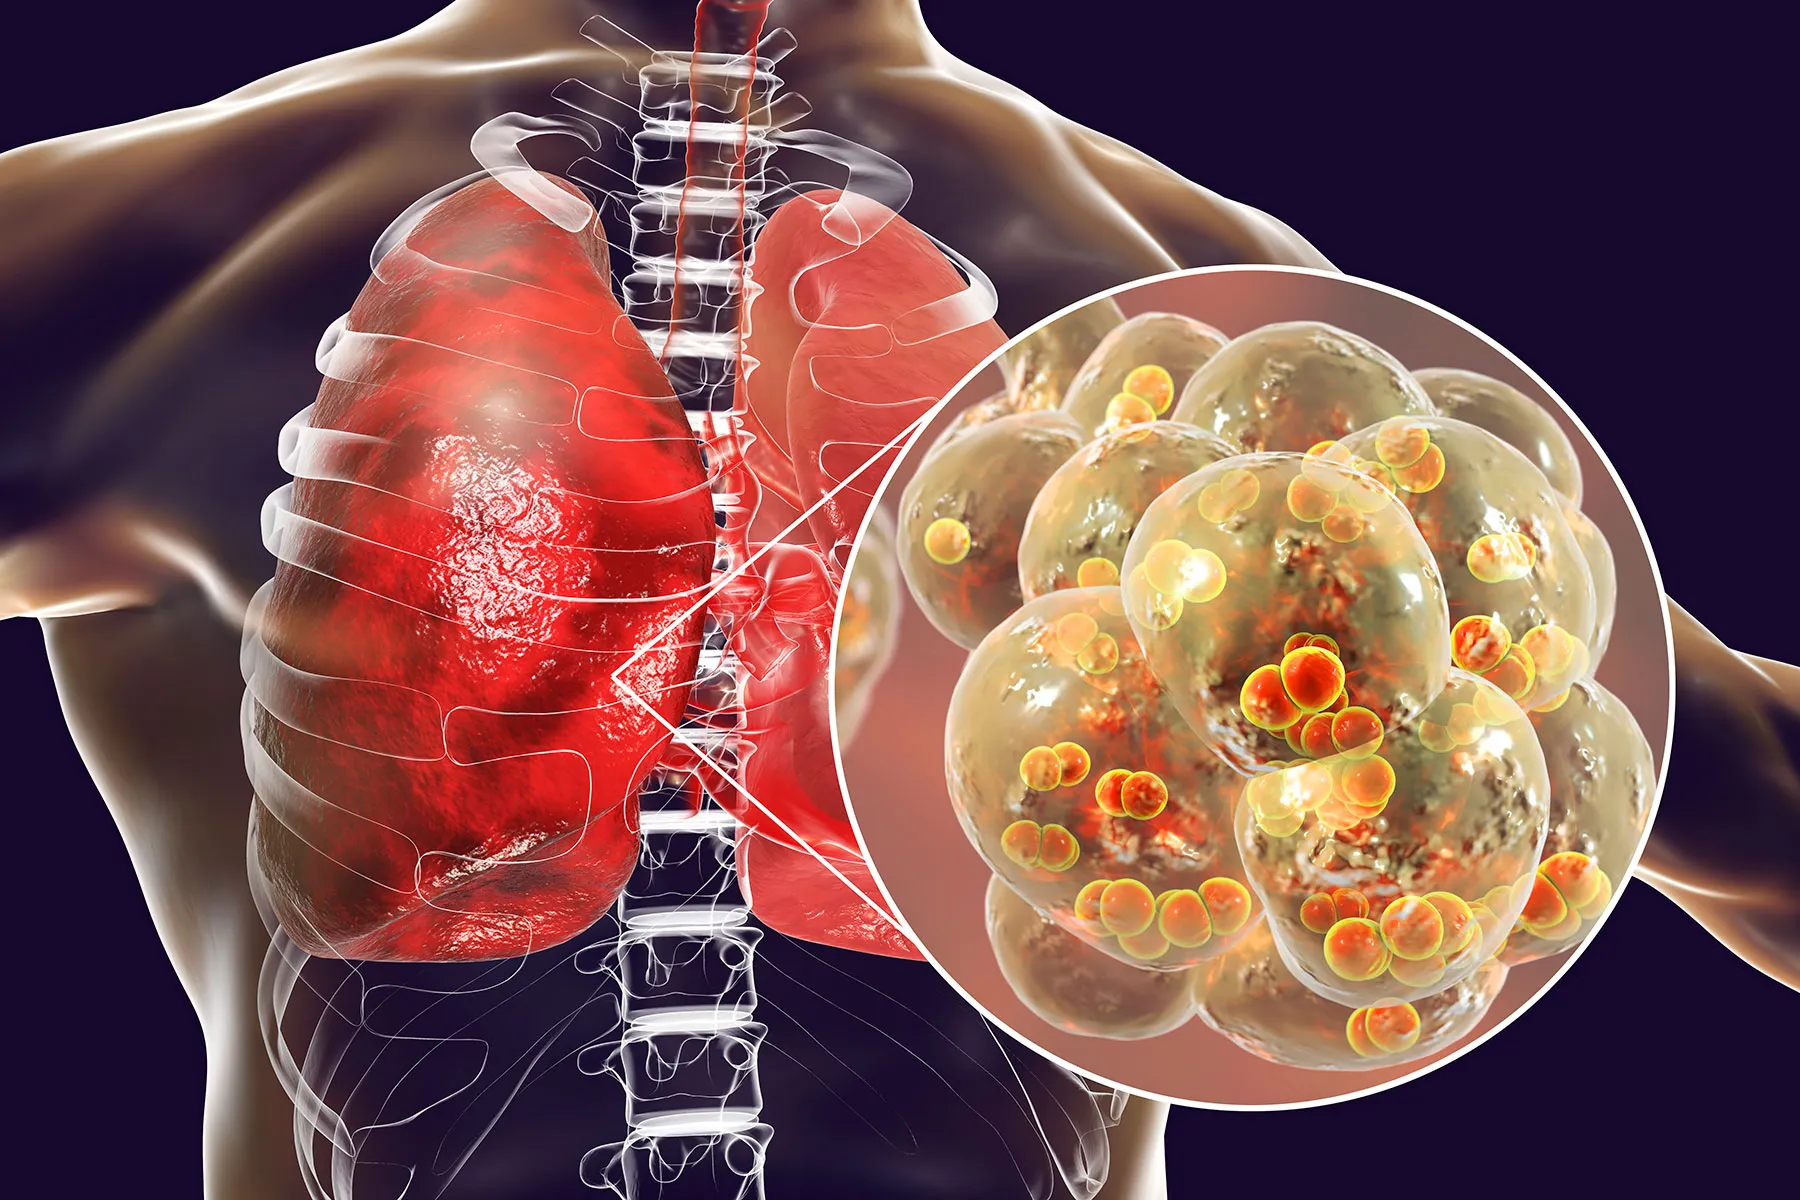

Evidence-based treatment protocols for the full spectrum of respiratory disorders — combining modern technology, advanced procedures, and personalised long-term care.

From everyday breathing problems to complex interstitial lung disease — Dr. Alwani offers expert diagnosis and individualised treatment for every major pulmonary condition.

We provide minimally invasive procedures that help diagnose and treat lung diseases with precision, safety and faster recovery — often as day-care visits under local anaesthesia.

Detects lung disease at the earliest stage — when it's most treatable.